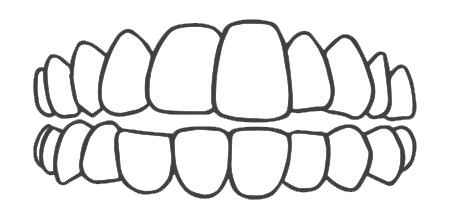

牙列间隙过大

深覆盖

牙列拥挤

深覆颌

开颌

前牙反颌